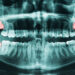

Burnos gydytojas pirmiausia apžiūri dantis ir dantenas, ieško patinimo ar kitų neįprastų požymių. Norint išsamiai įvertinti padėtį, dažnai atliekamos rentgeno nuotraukos – jos atskleidžia danties padėtį, šaknų eigą ir kaulo būklę po dantenomis.